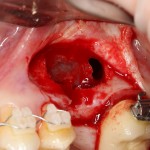

На фотографии ниже нам повезло — вы заметили перфорацию в ходе подготовки лунки под имплантат и приняли меры по ее устранению:

Однако, так везет далеко не всегда. Именно поэтому метод закрытого синуслифтинга имеет ряд ограничений: